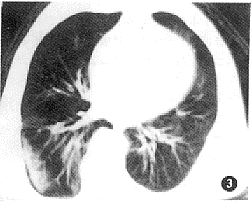

创伤性湿肺的CT表现是肺间质及肺泡的广泛挫伤和撕裂伤所引起的复合性改变。本组病例所显示的CT征象如下:(1)肺血管影增浓、模糊且粗细不均者16例(图1);(2)肺实质内散在斑点状、小片絮状稍高密度灶,边缘模糊不清者24例(图2);(3)呈磨玻璃改变的云雾状稍高密度灶,似一层薄纱复盖肺野(即“面纱征”)19例(图3);(4)大片状或呈叶、段分布的高密度灶,其内密度欠均匀,边缘不规则且模糊者20例(图4);(5)显示有大小不等、形态不规则的薄壁囊腔样低密度灶者16例(图5),囊腔内见小液平5例。上述CT表现在同一例中常混合存在。本组中CT发现有血气胸者16例,单纯血胸9例,单纯气胸6例,肋骨骨折17例,胸椎骨折3例,纵隔气肿4例,胸壁软组织积气10例,外伤性肺不张5例,肺内血肿9例。

图3 薄雾状面纱征,为肺创伤的特征性表现